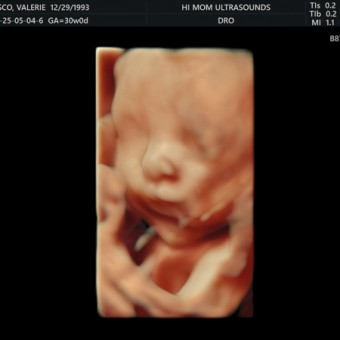

Valerie's Baby Registry

Valerie Nolasco & Joshua Rodriguez

July 13, 2025